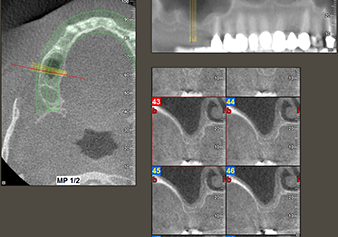

Following an intermediate check (Fig. 4) a further preparation step was performed (Fig. 5). Afterwards, the hydraulic Z35P instrument was used to lift the membrane to the desired position (Fig. 6 and 7). This was followed by further piezosurgical preparation of the implant bed, concluded with a rotary bur and shoulder milling cutter up to the implant diameter of 4.8 mm. Before the implant was inserted, the augmentation material (particle size approx. 0.8-1.6 mm) was introduced underneath the Schneiderian membrane (Fig. 8).

To move the augmentation material in the direction of the maxillary sinus atraumatically, the implant was inserted very slowly by hand (Fig. 9). In the process, the membrane was pushed in the cranial direction once again. After two months, the surgical site healed without irritation. Six months later, the x-ray check showed a significant increase in opacity as an indication of ossification (Fig. 10). The prosthetic restoration was carried out with a metal-ceramic crown.